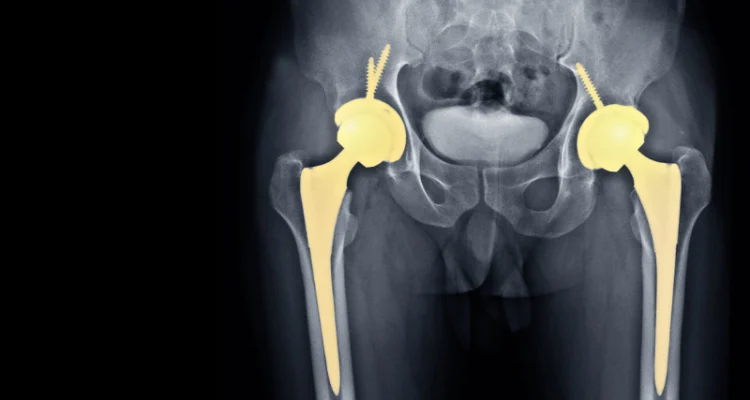

Total Kalça Artroplastisi (TKA) sonrası karşılaşılan en büyük komplikasyonlardan biri, implant bileşenlerinin birbirine fiziksel olarak temas etmesi sonucu oluşan “Impingement” yani sıkışma durumudur. Femoral boynun asetabular kap (yuva) kenarına çarpması, sadece hareket kısıtlılığına yol açmaz; aynı zamanda implantın yerinden çıkmasına (dislokasyon) veya polimer parçacıklarının aşınarak doku hasarına yol açmasına neden olabilir.

Statik sıkışma, protezin belirli bir açıda takılmasıdır. Ancak dinamik sıkışma, hastanın günlük hareketleri (yürüme, oturma, eğilme) sırasında femoral bileşen ile asetabular bileşen arasındaki etkileşimi ifade eder. Bu durum genellikle şu üç senaryo ile sonuçlanır:

- Protezden Proteze Sıkışma: Femoral boynun doğrudan asetabular metal kap kenarına vurması.

- Protezden Kemiğe Sıkışma: İmplantın çevre kemik dokularına teması.

- Sublüksasyon ve Dislokasyon: Sıkışmanın yarattığı manivela etkisiyle protez başının yuvadan çıkması.